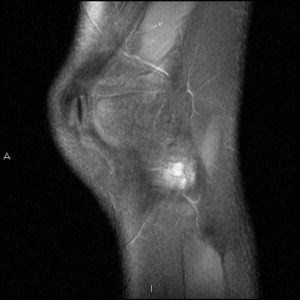

Когда появляется киста мениска коленного сустава, у человека не возникает специфической симптоматики. В данном случае даже опытному специалисту требуется использование дополнительных методов исследования для подтверждения своего предположения.

Проблемой обычно занимается врач-травматолог, который направляет пациента на УЗИ, КТ или МРТ.

Если болезнь находится на 3 стадии, то изменения в тканях колена можно рассмотреть с помощью рентгена.

В ряде случаев применяются артроскопия и пункция с изучением содержимого кисты. Методы диагностики позволяют точно определить место локализации, степень повреждения окружающих тканей, активность воспаления и размеры кисты.